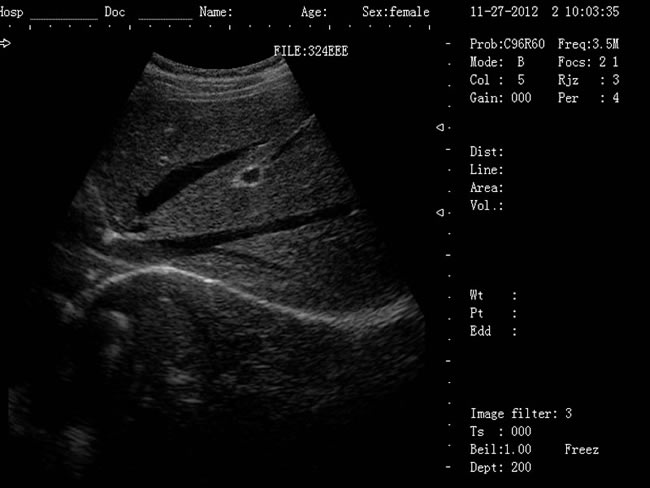

| 老式的b超機(jī)黑白要多少錢?已被新型B超機(jī)所取代! |

老式的b超機(jī)黑白要多少錢?老式的B超機(jī)是CRT顯示器,CRT顯示器學(xué)名為“陰極射線顯像管”,是一種使用陰極射線管的顯示器。現(xiàn)在科技進(jìn)步,已經(jīng)慢慢被新型顯示器所取代。老式的黑白b超機(jī)CRT顯示器主要有五部分組成:電子槍,偏轉(zhuǎn)線圈,蔭罩,高壓石墨電極和熒光粉涂層及玻璃外殼。感謝大家對我司CRT顯示器相關(guān)產(chǎn)品長久以來的支持與厚愛,該系列機(jī)型因順應(yīng)市場的需求,已經(jīng)無法滿足客戶的生產(chǎn)需求。該系列機(jī)型正式停產(chǎn),后期不再供應(yīng)該型號的儀器。給廣大的新老客戶造成的不便敬請諒解。應(yīng)廣大用戶的需要,CRT相關(guān)產(chǎn)品的售后服務(wù)依然支持,同時(shí)保留儀器后期的維修部件。

徐州大為DW-500筆記本b超機(jī) 1、DW-500產(chǎn)品特點(diǎn): (1)DW-500是一款高陣元、高清晰度、多功能的筆記本式超聲診斷儀。 (2)它的小巧輕便,圖像清晰,操作方便、續(xù)航能力強(qiáng),在城市、鄉(xiāng)鎮(zhèn)、戶外等,各種環(huán)境下會診的超強(qiáng)優(yōu)越性。 (3)多種充電方式更保證了在不同環(huán)境下檢查會診。 2、DW-500新增3大看點(diǎn): (1)5-7小時(shí)超長待機(jī)時(shí)間 (2)12.1英寸LED液晶顯示器 (3)全數(shù)字96陣元 3、一流的數(shù)字成像技術(shù),圖像更清晰 (1)DBF全數(shù)字波束形成 (2)DRF實(shí)時(shí)逐點(diǎn)動態(tài)接受聚焦 (3)DRA實(shí)時(shí)動態(tài)聲速變跡 (4)THI組織諧波成像 (5)RDA實(shí)時(shí)動態(tài)孔徑成像 (6)DFS數(shù)控動態(tài)頻率掃描 (7)RDF實(shí)時(shí)動態(tài)濾波 4、靈活方便的操作系統(tǒng) (1)12.1英寸LED液晶顯示器 (2)背光硅膠鍵盤,更舒適耐磨,暗室中使用不再煩惱 (3)智能化菜單,人機(jī)對話輕松快捷 (4)顯示穿刺引導(dǎo)線,角度和位置可調(diào) (5)多倍率顯示,病變診斷更準(zhǔn)確 (6)外接USB存儲,圖像上傳更方便 (7)大容量的電影回放,圖像自動循環(huán)演示 (8)豐富的測量功能:距離,周長,面積,體積,產(chǎn)科測量表,心臟軟件包等 (9)顯示模式:B、B+B、4B、B+M、M (10)電影回放:≥256幀,可連續(xù)回放或逐幅查看 (11)具有穿刺引導(dǎo)功能,穿刺線位置可調(diào)節(jié) (12)具有碎石定位,動態(tài)靶區(qū)跟蹤功能 (13)主機(jī)尺寸:330x289x70mm(長x寬x高);